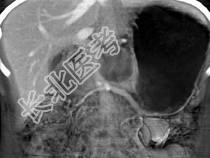

- 单项选择题患者16岁,女性, 最可能的诊断是 ( )

D、胰腺胚细胞瘤